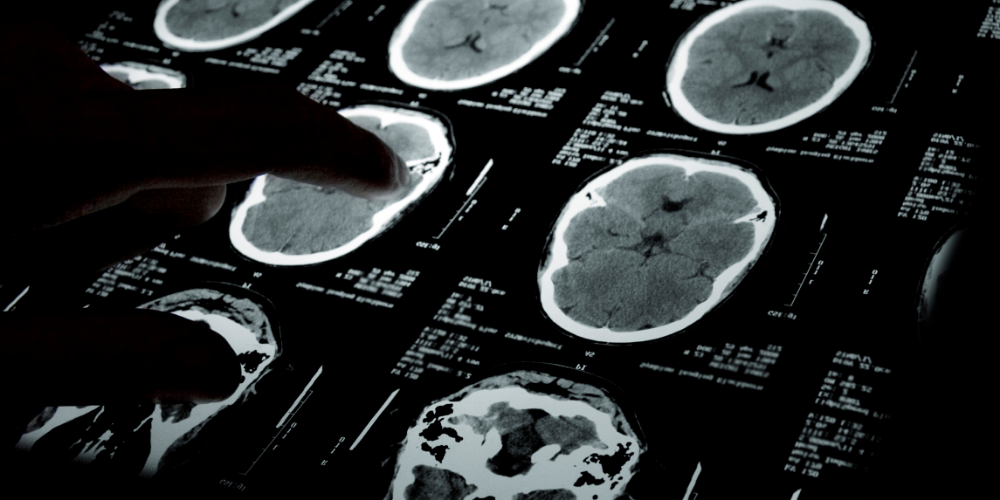

La terapia consiste nell’infondere nel cervello un virus modificato che rilascia una sequenza di DNA capace di ridurre i livelli della proteina huntingtin mutata, responsabile della morte dei neuroni. L’intervento richiede 12-18 ore di neurochirurgia guidata da risonanza magnetica.